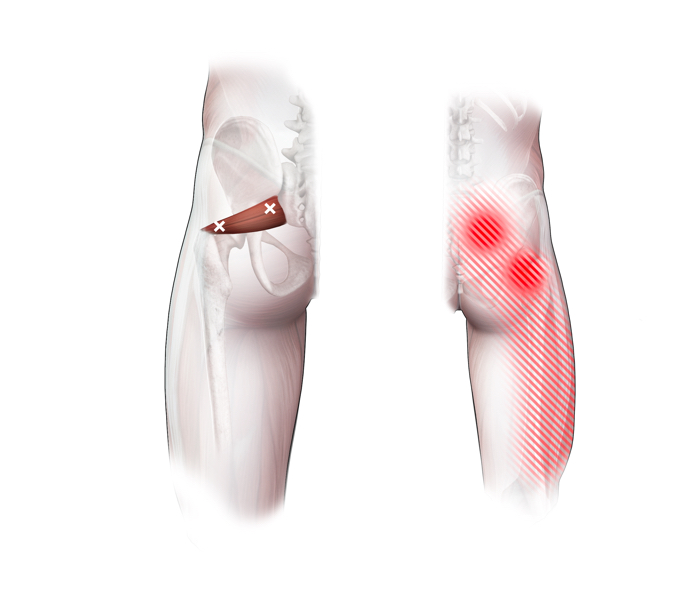

Spieren (Nederlands)

Spieren (nederlands)

Spieren (Latijn)

Spieren (latijn)